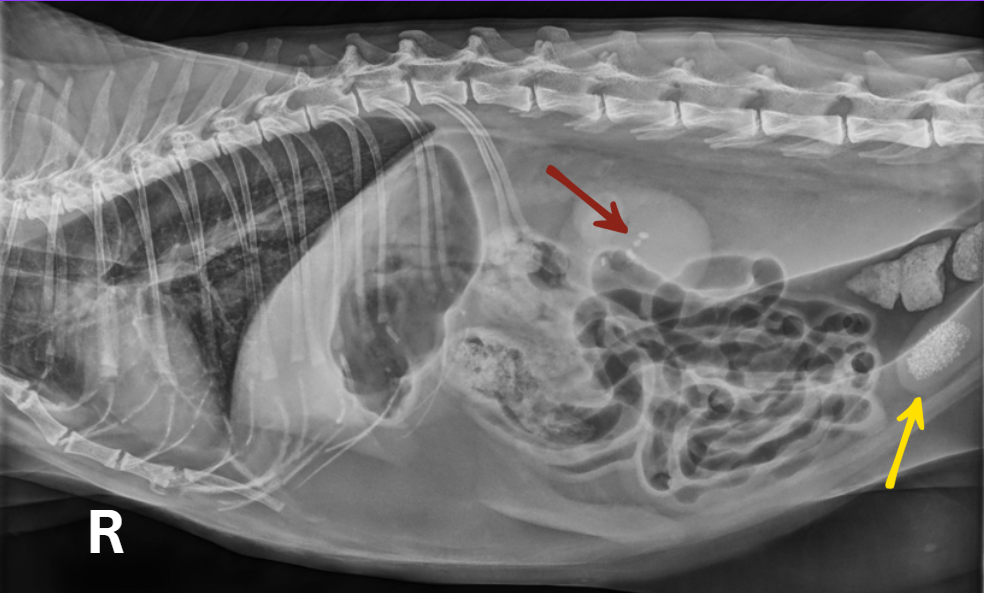

Uroliths (or stones found in the bladder (Yellow Arrow) and kidneys (Brown Arrow) of a feline patient during radiographs